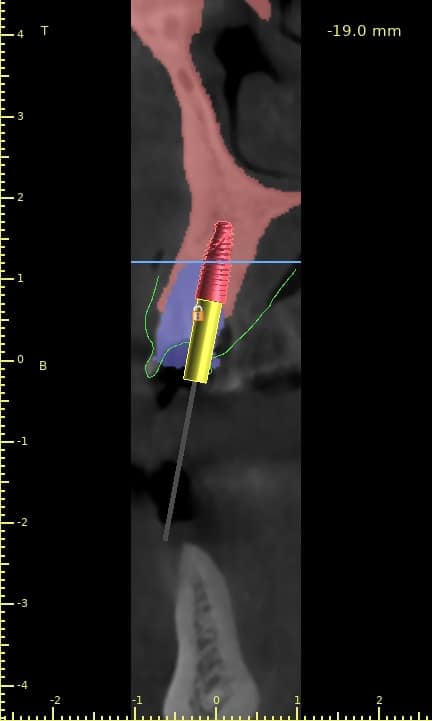

Case of the day where i extracted the 34-35-36 and an immediate placement of 2 implants in the 34-36 sites

sticky bone grafting GTO by osteobiol was used with straumann xenograft